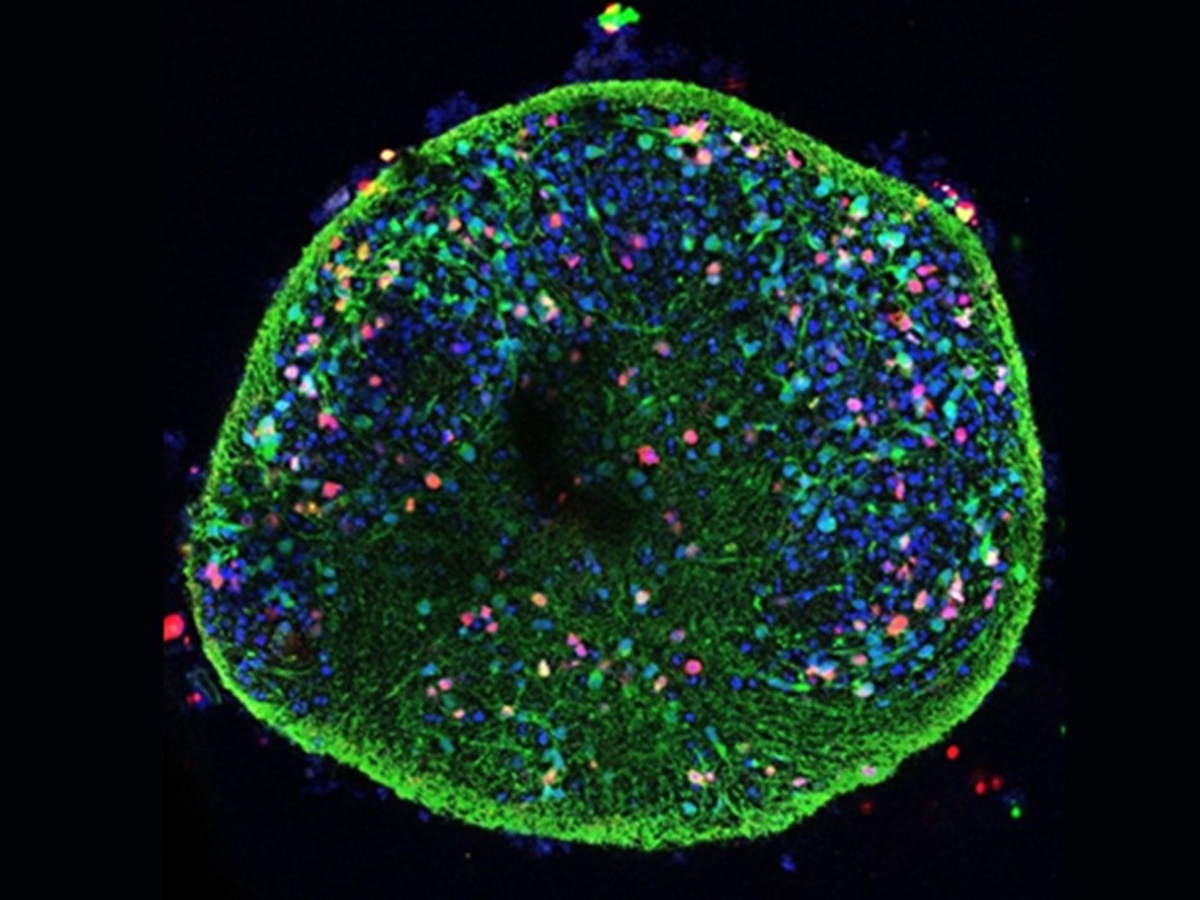

Alteraciones celulares del Alzheimer, observadas también en cultivos de neuronas infectadas por virus del herpes labial CSIC

“Estos modelos tridimensionales permiten que las células crezcan formando agregados que imitan mejor la organización del tejido nervioso humano, reproduciendo, de forma más realista, las interacciones y el entorno que existen en el cerebro”, ha explicado Jesús Aldudo, también investigador del CBM. En este sistema, las neuronas se agrupan en pequeñas esferas (esferoides) y, gracias al entorno 3D, se proyectan en todas las direcciones, crean redes más sofisticadas y se ordenan en capas, algo mucho más cercano a lo que sucede en el tejido cerebral que lo que permiten los cultivos planos convencionales.

El estudio concluye que el virus del herpes labial altera un sistema clave de limpieza celular encargado de eliminar y reciclar proteínas dañadas o sobrantes. Cuando este mecanismo se ve comprometido, las proteínas defectuosas se acumulan y se favorecen procesos de neurodegeneración. Para los autores, se trata de un hallazgo especialmente importante, ya que estos efectos se observaron tanto en cultivos celulares sencillos como en modelos en 3D, donde el virus logró infiltrarse en toda la estructura neuronal y desencadenar las mismas alteraciones moleculares asociadas al Alzheimer.